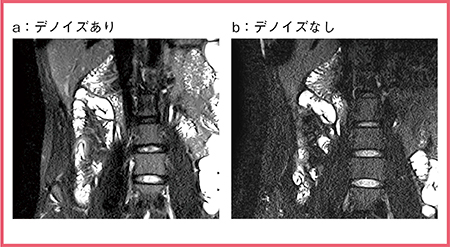

TRILLIUM OVALのデノイズ処理(W.I.P.)も有用である。図3は,同一患者の画像をデノイズの有無で比較しているが,デノイズあり(a)の方が全体にノイズが低減され,回腸末端部の病変や背景信号のコントラストが明瞭である。

図3 デノイズ処理による回腸末端の病変のコントラスト向上

(参考文献7)より引用転載)